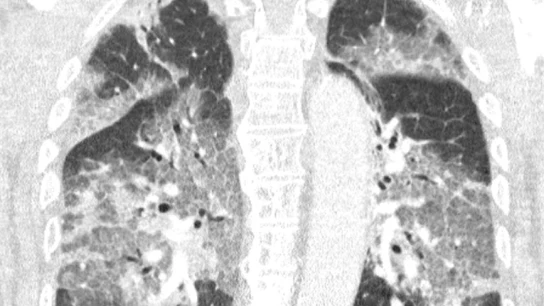

"El virus lo había atacado y podía haberse evitado": con una imagen de unos pulmones destrozados y una dura carta abierta, los sanitarios de un hospital neerlandés piden así al ministro de Sanidad que reconsidere la suspensión de la vacunación con AstraZeneca.

"Hoy ingresamos en nuestro hospital al primer paciente que se había negado a la vacuna AstraZeneca después de toda la conmoción de la prensa. Oímos el enorme pesar en su voz y vimos la desesperación en sus ojos. El virus lo había atacado y podía haberse evitado", comienza la misiva, que desmonta con datos el miedo a AstraZeneca: "No es necesario ser un especialista en pulmones para ver su devastación, ni ser epidemiólogo para explicar los riesgos de no estar vacunado".